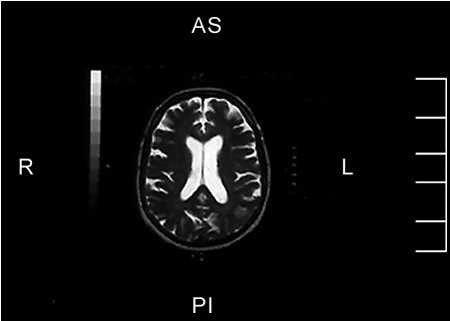

La paciente es una mujer de 69 años que consultó a la Clínica Las Condes por una afasia receptiva completa (afasia de Wernicke) de dos horas de evolución. La paciente tenía antecedentes de arritmia cardíaca (fibrilación auricular) pero no estaba recibiendo sus medicamentos de anticoagulación. De inmediato se efectuó una tomografía axial computada (TAC) cerebral, la que no mostró evidencias de hemorragia ni cambios precoces de infarto cerebral. En ese momento se decidió que la paciente era una buena candidata para trombolisis y se comenzó una infusión endovenosa de tPA (10% dosis según peso en bolo y 50% de dosis total en 45 minutos) con una dosis reducida de trombolisis EV. También se le inyectó el radiofármaco Tc99mHMPAO para posteriormente obtener un NeuroSPECT inicial. A continuación se efectúo una angiografía cerebral la que mostró una oclusión de la rama angular de la arteria cerebral media izquierda, probablemente de origen cardioembólico (Figura Ia). Se avanzó un microcatéter hasta la oclusión (Figura 1b) y se comenzó la trombolisis IA local, al mismo tiempo que se detuvo la infusión endovenosa de tPA después de haber recibido una dosis total de 24mg tPA EV. Al cabo de una hora, fue posible obtener una completa recanalización del vaso ocluido inyectando IA un total de 20 mg de tPA. Inmediatamente de haber recanalizado este vaso (Figura 1c y 1d), la paciente se recuperó de su afasia. El examen de NeuroSPECT pre-trombolisis demostró una zona de hipoperfusión profunda en el territorio de la arteria angular Figs. 2a y 2b.. La paciente ingresó a la Unidad CerebroVascular para un manejo médico especializado incluyendo manejo hemodinámico, anticoagulación después de las primeras 24 horas y manejo de su arritmia cardíaca. Un segundo NeuroSPECT de control a las 24 horas post-trombolisis, demostró una completa recuperación de la perfusión cerebral en el territorio de la arteria ocluida (Figura 2c y 2d). Por último, una resonancia magnética de cerebro (Figura 3) no reveló ninguna evidencia de infarto cerebral. La paciente fue dada de alta a los siete días sin ningún déficit neurológico.